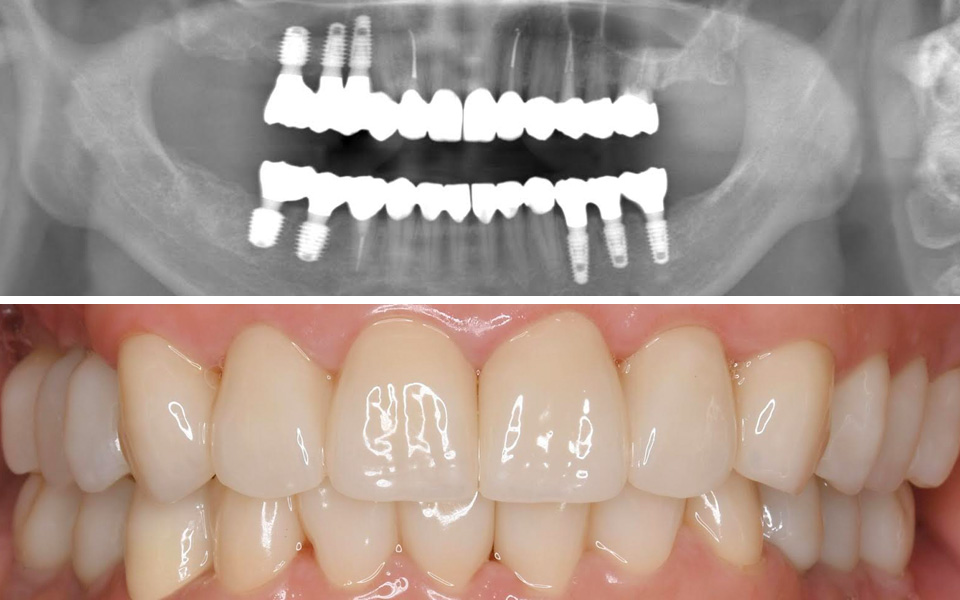

インプラント症例Case

差し歯が取れてしまい困っている:30代女性

治療内容

歯根がほとんど残っていないため、歯を残すことは不可能でした。

インプラント治療による審美性の回復を目指しました。

抜歯即時埋入インプラントを行うことで、抜歯と同時のインプラント埋入と仮歯のセットまで行いました。

治療部位

上・前歯

費用

462,000円(税込)

右上の奥歯がないので、噛めない:40代女性

治療内容

十分な骨量があるケースでしたので、即時荷重インプラントを行いました。

インプラントの埋入オペ→同時に仮歯のセット→6週間待つ→セラミック歯の型取り→2週間待つ→セラミック歯のセット→噛み合わせのチェック という流れで

治療スタートから2ヶ月半後には、インプラント治療が完了しました。

治療部位

上・右奥歯

費用

1本あたり 440,000円(税込)

総額 880,000円(税込)